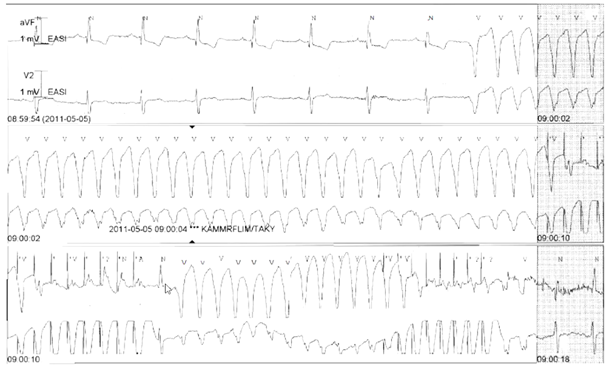

Vad beskrivs?

CRT (hjärtsviktspacemaker)